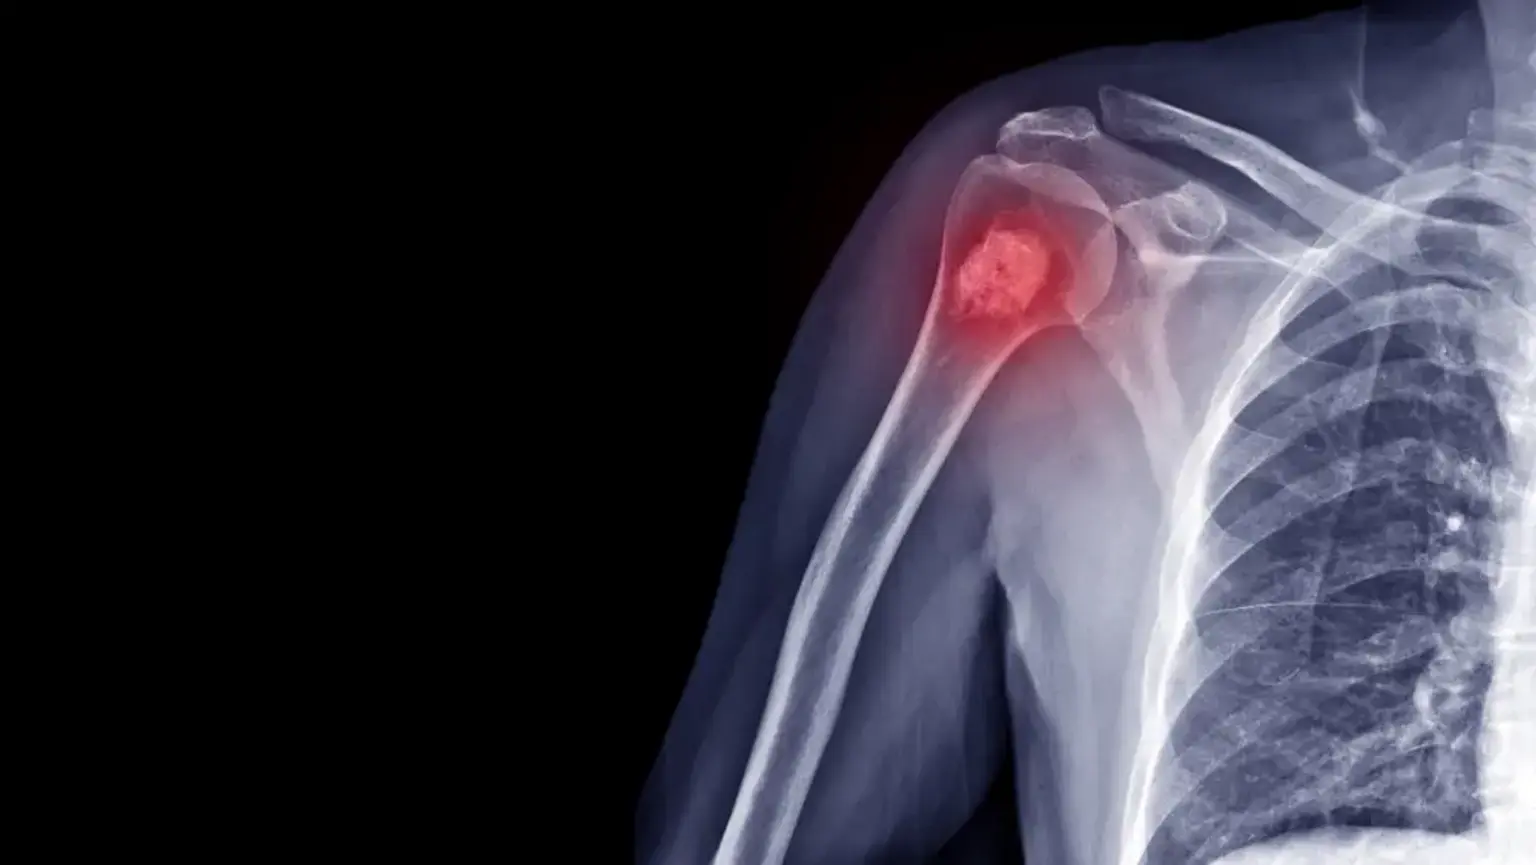

• X-ray: Often the first test performed to identify a potential tumor.

These malignancies can develop in any of the body's 206 bones but most commonly occur in the long bones of the arms and legs, as well as the pelvis. The cancerous cells destroy normal bone tissue, which can lead to pain, fractures, and other complications. Globally, primary bone cancers account for less than 1% of all cancers.

• Unexplained Fracture: The cancer can weaken the bone, leading to a fracture from a minor fall or sometimes with no injury at all. This is known as a pathologic fracture.